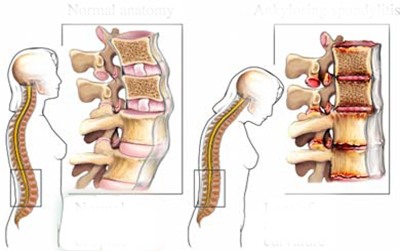

Đây là hiện tượng thoái hóa đốt sống cổ, tổn thương nặng vùng cơ trên phần cổ, cần phải lập tức điều trị phục hồi chức năng, trị liệu nhanh để hồi phục công năng hoạt động của cổ.

Theo bác sĩ Hồ Tiểu Quân, trẻ em trong một thời gian dài ngồi yên một chỗ để chơi iPad, điện thoại di động sẽ gây ra đau cơ cổ, căng thẳng, co thắt dây chằng, nếu không can thiệp, nguy cơ trong tương lai sẽ bị thoát vị đĩa đệm cổ và các bệnh khác.

Ngoài ra, xương của trẻ em đang trong giai đoạn phát triển, căn bệnh này có thể ảnh hưởng đến kích thước của đốt sống cổ, phát triển dị dạng, trường hợp nghiêm trọng thậm chí có thể ảnh hưởng đến ngực, thắt lưng và các phần xương khác, thậm chí làm hạn chế phát triển chiều cao.

Khi trẻ em chơi trò chơi, chúng sẽ ngồi yên "bất động" và giữ tư thế đó trong một thời gian dài. Lâu và thường xuyên như vậy, cổ sẽ cúi gập xuống gây võng xương.